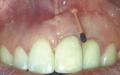

Лечение ретроградного периимплантита с использованием направленной костной регенерации

Ретроградный периимплантит (РПИ) характеризуется атипичной и часто прогрессирующей потерей костной ткани в периапикальной области дентального имплантата. Хотя, по имеющимся данным, распространенность РПИ ниже, чем маргинального периимплантита, при отсутствии лечения это состояние может привести к потере имплантатов. В данной клинической серии случаев два пациента с различными проявлениями РПИ были пролечены с использованием направленной костной регенерации (НКР) с применением костного трансплантата и коллагеновой мембраны. Долгосрочное наблюдение показало клиническое и рентгенологическое улучшение, которое выразилось в рентгенологическом костном наполнении и уменьшении глубины зондирования вокруг имплантатов. Наблюдения, представленные здесь, позволяют предположить, что НКР при дефектах, вызванных РПИ, является эффективным методом лечения.